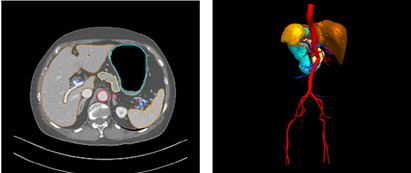

目前针对血管堵塞诊断,仍旧完全依赖于医生的主观意识完成。临床上缺乏一种对血管狭窄度、堵塞程度等进行分析的辅助诊断工具。我们的作品应用冠状动脉血管堵塞辅助诊断技术,即将人工智能技术应用于辅助诊断诊疗中,让计算机“学习”专家医生的医疗知识,模拟医生的思维和诊断推理,从而给出可靠诊断和治疗方案,从而极大地降低医生的工作量。

中国是一个胃癌发病和死亡高发的国家。从发病率来看,仅次于肝癌,位居第二位。由于中国的人口基数非常大,目前胃癌发病总人数占全世界约47%,即将近一半的胃癌病人在中国。究其原因一是我国早期胃癌的检出率低,二是诊治流程的规范化程度低,三是胃癌手术操作的规范化程度尚未在基层医院建立。首诊医生对胃癌患者的处理,将直接影响患者的预后。决定医生制订治疗方案的最重要一环,就是医生对患者的胃癌术前分期判断,因为只要分期判断准确,结合NCCN指南和胃癌专家共识中国版,就可以按图索骥地给出合理的治疗方案。胃癌与淋巴结的大小与位置等特征是胃癌分期重要的参考。基于深度学习的人工智能技术在胃癌诊断中的应用目的在于构建和验证一个用于早期胃癌自动识别的深度学习模型,提高早期胃癌的识别和诊断水平。